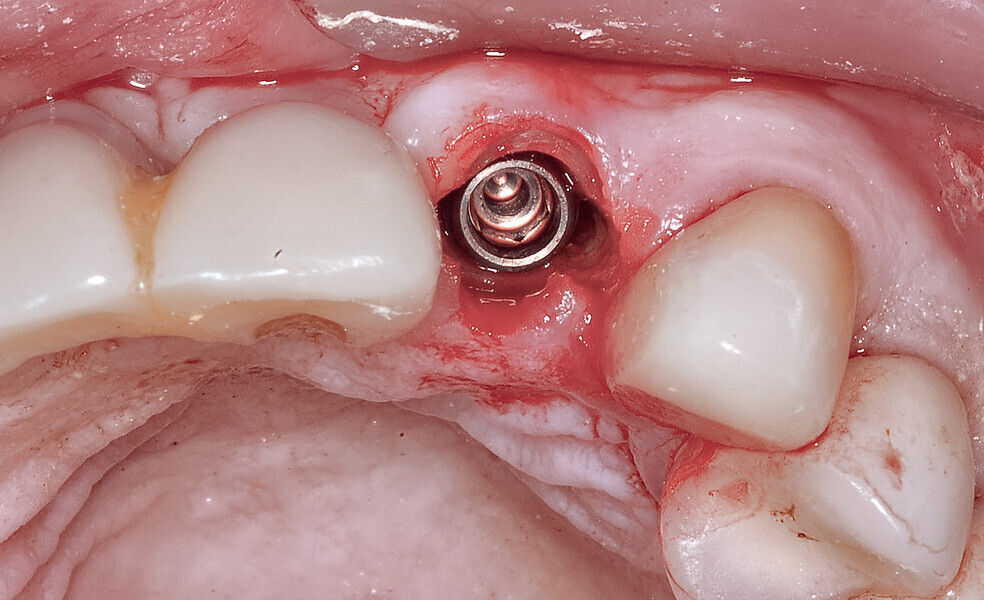

Fig. 23: The implant, seen prior to placement,

using the R2GATE surgical carrier for full-template guidance through the sleeveless guide.

Fig. 24a: Depth control and rotational positioning were accurately

confirmed with the notch indicator on the template corresponding with the insertion tool (a). The occlusal view illustrated that the anti-rotational internal

conical–hexagonal connection was positioned towards the facial aspect (b).

Fig. 24b: Depth control and rotational positioning were accurately

Fig. 25: Using an implant-specific SmartPeg, a baseline ISQ value of 76 confirmed sufficient initial stability to place an immediate restoration.